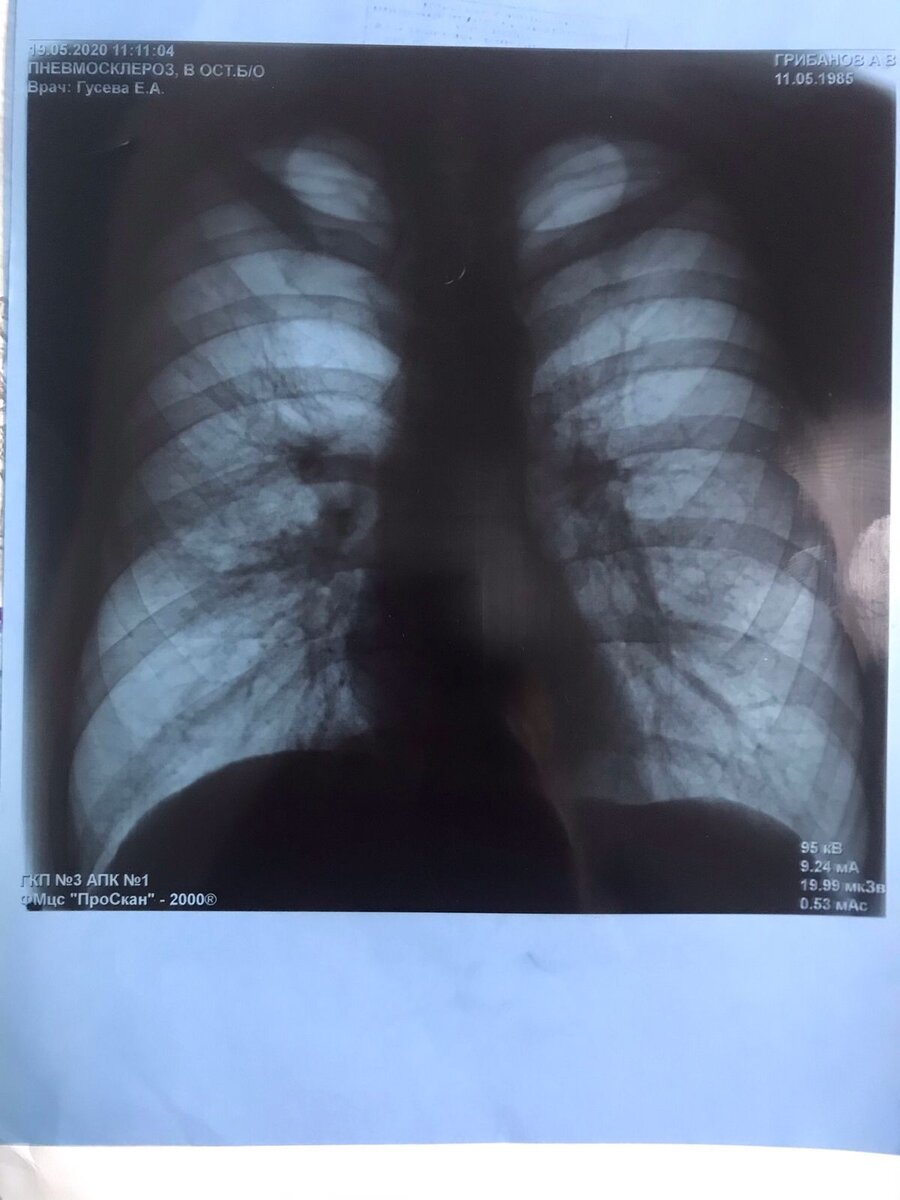

Фото взято не из открытых источников. Это прям мой снимок, но до болезни... за пол года до.

Так вот... в отличии от людей не болеющих диабетом, люди им болеющие в большей группе риска. С диабетом, особенно если сахара не компенсированны (ну то есть скачет как кардиограммы после спринта в гору), туберкулез прогрессирует быстрее. У меня спрогрессировал туберкулез за шесть (+-) месяцев... знаю, ибо флюорографию делаю всегда вовремя. И за пол года спрогрессировала болезнь довольно сильно, стадия распада и прочее.